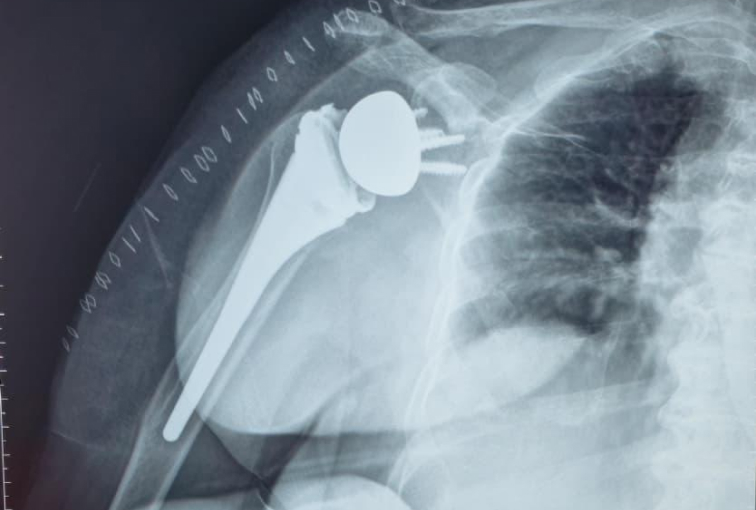

Seeking the blessings of His Holiness Jagadguru Dr. Sri Shivaratri Rajendra Mahaswami ji and offering our humble pranams to His Holiness Jagadguru Sri Shivarathri Deshikendra Mahaswami ji, JSS Hospital has achieved a historic milestone in healthcare. For the very first time in Mysuru, the Department of Orthopedics successfully performed a Reverse Total Shoulder Arthroplasty (RTSA) using state of the art Virtual Implant Positioning (VIP) technology by Arthrex.

Reverse Total Shoulder Arthroplasty is a sophisticated surgical solution designed for patients with severe shoulder dysfunction, particularly when conventional shoulder replacement proves ineffective. Individuals suffering from persistent pain, difficulty with daily activities such as combing hair or reaching the back, and pseudo-paralysis caused by rotator cuff insufficiency can benefit significantly from this approach. In this technique, the shoulder’s natural ball-and-socket orientation is reversed, where the glenoid socket becomes the humeral head and the humeral head assumes the role of the socket.

This modification empowers the deltoid muscle to compensate for damaged rotator cuff muscles, thereby restoring function and improving quality of life.

Initially reserved for irreparable cuff tear arthropathy, Reverse Shoulder Arthroplasty has now expanded in scope. It is increasingly considered for patients with primary osteoarthritis, complex proximal humeral fractures (especially Neer’s four-part fractures), and tumors. The decision to perform RSA takes into account patient-specific factors such as age, bone quality, activity levels, and the degree of rotator cuff compromise.